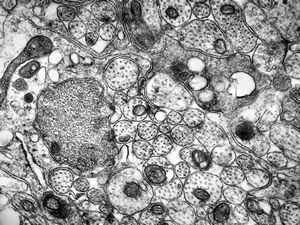

F,50y. | progressive multifocal leukoencephalopathy- viral particles in a glial cell

F,50y. | progressive multifocal leukoencephalopathy- viral particles in a glial cell

F,50y. | progressive multifocal leukoencephalopathy- viral particles in a glial cell